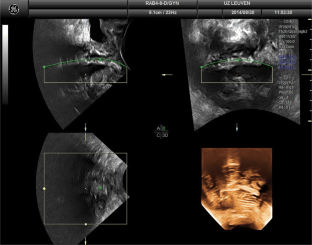

There were 17 women in the PP and 25 in the PVDF mesh group, without differences in baseline demographics. None had significant prolapse, recurrence, symptoms, or complications. On TPUS, mesh was visible in all patients both caudally (perineal) and cranially but was more echogenic in the PVDF mesh group. Mesh length from distal to proximal that was visible on TPUS was longer for PVDF mesh, for both anterior and posterior vaginal arms (all P < 0.05), and for mesh above the vaginal apex (P = 0.002). The inferior aspects of the mesh showed areas of double mesh layers, suggesting folding in 80% of women in both groups, without symptoms.

Fig. 2